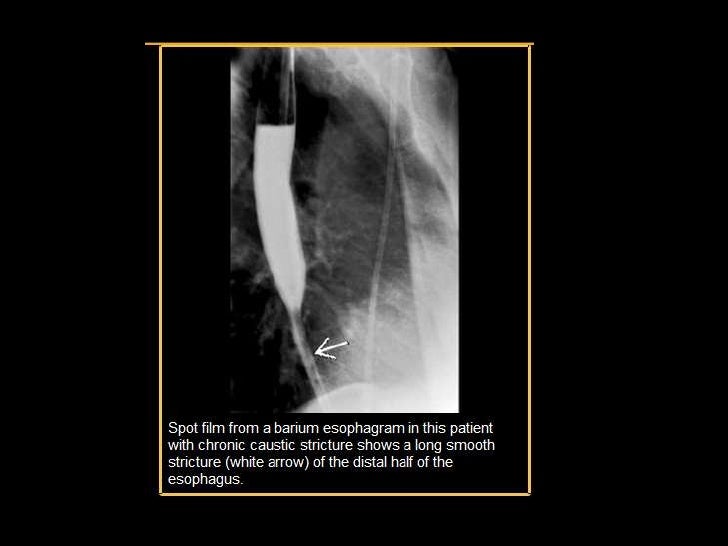

Figure 2Benign Strictures of the Esophagus and Gastric Outlet Caustic Esophagitis — esophageal motility studies report low amplitude and nonperistaltic. — caustic substances injure tissue by means of a chemical reaction on direct physical contact. — caustic ingestion can cause severe injury to the esophagus and the stomach. — caustic ingestions are seen most often in young children between one and three years of age and can. Caustic Esophagitis.